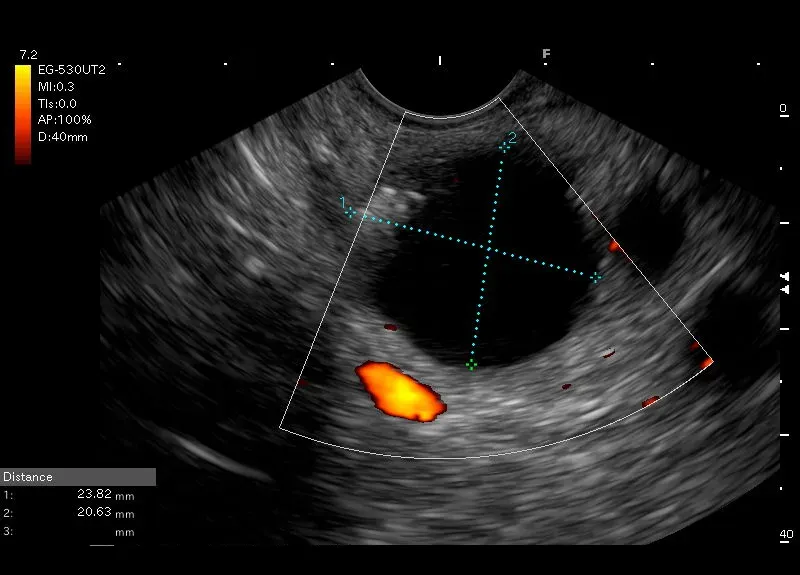

Widoczna w dystalnej części trzonu trzustki bezechowa, owalna przestrzeń o morfologii torbieli z hyperechogeniczną przyścienną strukturą odpowiadająca zwapnieniu przyściennemu.